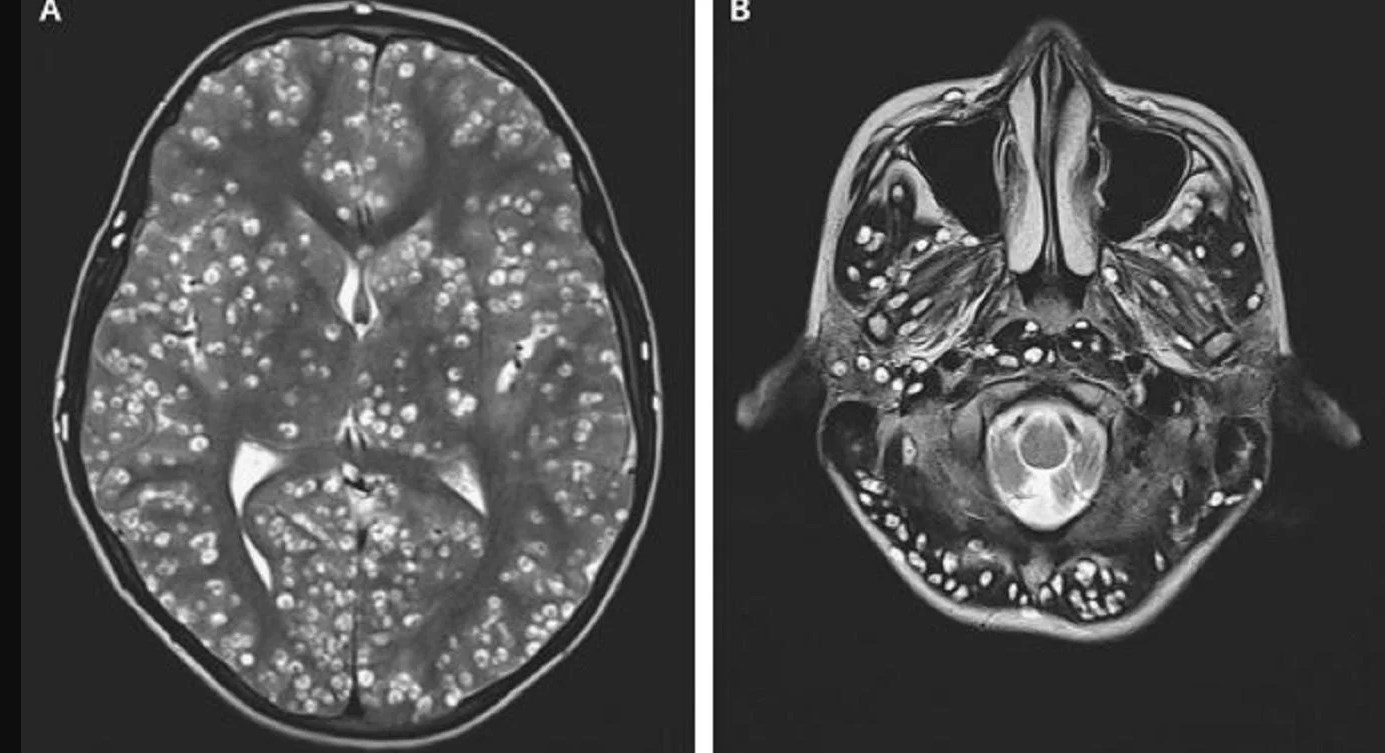

Un adolescente de 18 años fue trasladado de urgencia a un hospital en Faridabad, India, luego de sufrir convulsiones. Dada la seriedad del cuadro que presentaba, los médicos ordenaron la inmediata realización de una resonancia magnética de su cerebro. Al recibir el resultado del estudio, fueron testigos de una realidad terrible: estaba lleno de gusanos.

El caso del joven, cuya identidad no trascendió, fue publicado en el New England Journal of Medicine junto con las imágenes obtenidas de su cerebro. Según el reporte, el paciente ingresó al establecimiento en estado de confusión, con el ojo derecho inflamado y con dolor en la ingle, por lo que pidieron hacerle una tomografía.

Para asombro de los profesionales, el estudio mostró que tanto las convulsiones como las lesiones en su cuerpo habían sido causadas por la presencia de quistes producidos por la Taenia Solium, un parásito que se transmite por la ingesta de carne de cerdo cruda o mal cocida.

A través de la producción de huevos, el gusano es capaz de esparcirse rápidamente por el organismo, generando quistes y dañando los tejidos, en una enfermedad conocida como cisticercosis. Lamentablemente, la cantidad de lesiones en el cerebro del adolescente era tan grande que los médicos no pudieron hacer nada para salvarle vida, y falleció luego de dos semanas bajo tratamiento con dexametasona y medicamentos antiepilépticos.